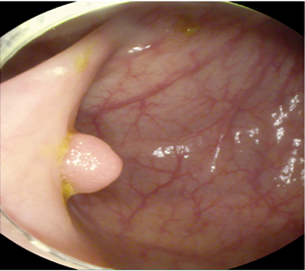

The study used a publicly available dataset of polyp-frames obtained from the ETIS-Larib database [34], containing 196 polyp images. These images were obtained from 34 different colonoscopy videos of 44 different polyps with various appearances and sizes, having a resolution of pixels. The ground truth of polyp areas for polyp datasets is determined by expert video endoscopists. A CNN model trained with such a small amount of data is likely to be meaningless and unstable, so data augmentation was performed on the polyp dataset. Data augmentation had to be performed on the colonoscopy images by considering vivid variations. Otherwise over-fitting would have occurred. In a colonoscopy imagery, polyps exhibits large variations in location, color, and scale. Moreover, variations in brightness and definition also occur due varrying the view-point of the camera. Therefore, in addition to photometric distortions and geometric distortions, we also have considered zooming, shearing, and altering brightness as strategies for data augmentation.

For photometric distortions, we controlled brightness and contrast as an enhancement, while blurring by adding noise with a standard deviation of 1.0. Similarly, for geometric distortions, clock-wise rotation of the polyp images with angles of , , and were performed. Zoom-in and zoom-out with zooming parameters such as 30.00% and 10.00% were performed to obtain different scales of polyp images. Lastly, shearing for both the x-axis and the y-axis was performed to shear the images from left to right and top to bottom, respectively. Fig. 4 shows photometric and geometric forms of image augmentation. In this way, we augmented the data set of the ETIS-Larib database from 196 polyp images to 2,156 images, which is more suitable for training the proposed deep CNN model.

The results shown in Fig. 6 are generated using the proposed deep CNN model on the augmented data set. It can be observed that the proposed model shows better polyp detection performance. As illustrated in Fig. 6, polyps within a frame can be identified at multiple positions, and as noted above in this case, the TP for detection is considered to be 1. The proposed deep CNN model performed better than other benchmark results in terms of the performance metrics listed above, as shown in Table. 2 and Fig. 6.